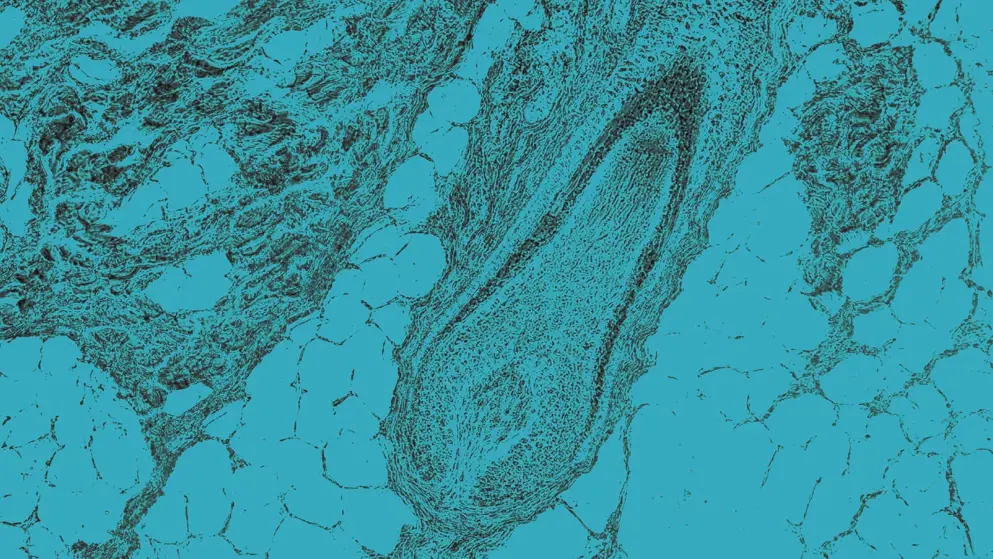

Scalp and hair follicles, cellular image, blue overlay

Alopecia areata (AA) is caused by the immune system erroneously attacking hair follicles, leading to inflammation. While researchers are not entirely sure why this immune attack occurs, they suspect that both genetic and environmental factors contribute. AA mainly causes hair loss, though it can sometimes cause changes in the nails, such as pits. People with this condition are generally healthy and exhibit no other symptoms.